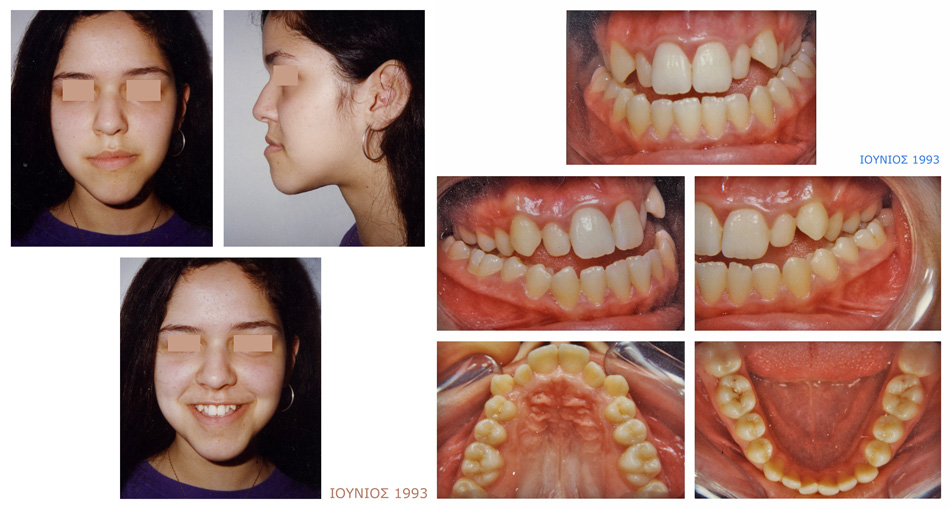

Χειρουργικά Περιστατικά

Στένωση και συνωστισμός στην άνω γνάθο. Έντονος προγναθισμός της κάτω γνάθου με διάστημα μεταξύ άνω και κάτω δοντιών.

Έγινε ορθοδοντική θεραπεία ως προχειρουργική αγωγή, ακολούθησε γναθοχειρουργική επέμβαση στην κάτω γνάθο και τελείωσε με την μεταχειρουργική ορθοδοντική αγωγή.

Πριν τη Θεραπεία